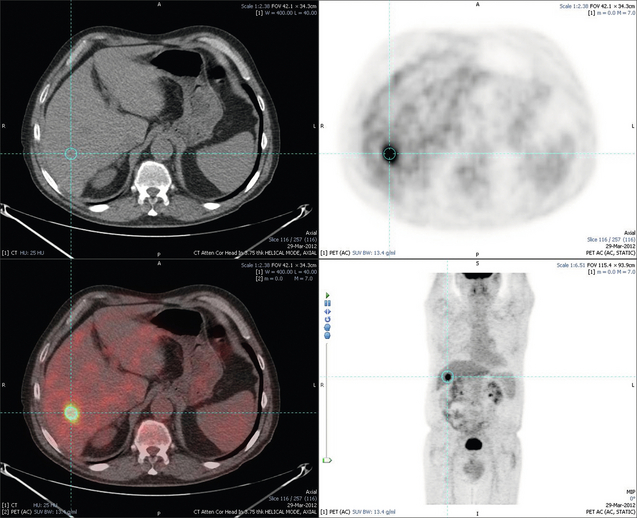

Uma vez diagnosticada a lesão, a presença de dois exames de imagem (geralmente tomografia computadorizada e ressonância nuclear magnética) com achados típicos é considerada suficiente para o diagnóstico, não sendo necessária a realização de biópsia na maioria dos casos.

Quando o tumor é grande demais para ser considerada a possibilidade de transplante ou cirurgia, existe a possibilidade de reduzir o seu tamanho através de quimioembolização (TACE), que é um procedimento onde o radiologista intervencionista identifica a artéria que está nutrindo o tumor, injeta uma dose de quimioterápico direto na lesão e entope a artéria para “matar” o câncer. Apesar de ser considerado um tratamento paliativo ou como “ponte” para o transplante, também pode curar. Uma variação mais recente desse tratamento, que cada vez fazemos mais, é a radioembolização, onde ao invés de um quimioterápico injetamos microesferas radioativas.